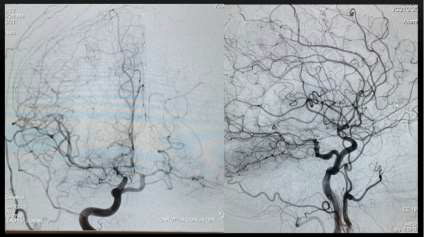

De acordo com o achado da angiografia abaixo, assinale a alternativa CORRETA.

Fonte da Imagem: cedida pelo autor

Provas